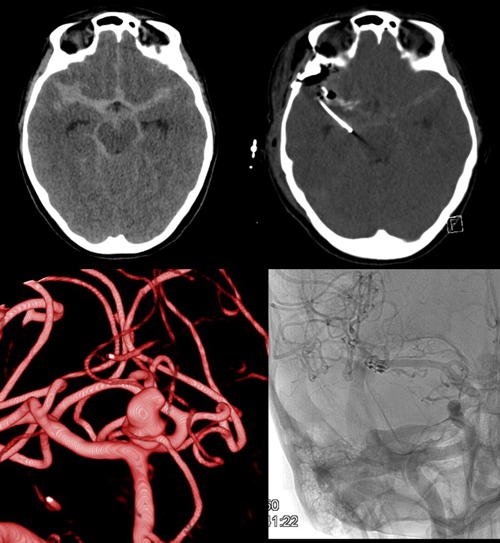

Severe head injury and aneurysmal SAH (Fig. 4) as well as haemorrhagic strokes are common medical conditions in the department. As well as multimodal monitoring and numerous pathophysiological investigations, various multi and monocentric studies are regularly undertaken. Invasive multimodal neuromonitoring of brain oxygenation, metabolism, blood flow and intracranial pressure alongside advanced imaging and targeted metabolomic profiling are performed for continuous evaluation of these techniques in treatment optimisation and patient outcome after subarachnoid haemorrhage and severe/moderate head trauma.

- Dual ICP: Simultaneous application of multimodal invasive neuromonitoring in both intracranial supra/infratentorial compartments of patients with posterior fossa lesions, to obtain additional comprehensive data from the entire brain.

- NICAPLANT: Phase-IIb trial of nicardipine prolonged release pellets in aneurysmatic subarachnoid haemorrhage.

- TIBI I/II: Multimodal invasive neuromonitoring in patients with severe and moderate head trauma in combination with early MRI and targeted metabolomics, identifying CFS and serum biomarkers of neuronal injury.

- PREVAIL: Pilot trial of autologous intravenous CSF transfusion for the prevention of cerebral vasospasm after SAH.

- Cerebral vasospasm and delayed cerebral ischaemia after aneurysmal SAH – European / North American surveys and transnational cohort studies.

- Pinggera D, Steiger R, Bauer M, Kerschbaumer J, Luger M, Beer R, Rietzler A, Grams AE, Gizewski ER, Thomé C, Petr O. Cerebral Energy Status and Altered Metabolism in Early Severe TBI: First Results of a Prospective 31P-MRS Feasibility Study. Neurocrit Care. 2020 Jul 2. doi:10.1007/s12028-020-01042-x. Epub ahead of print.

- Ho WM, Görke AS, Glodny B, Oberacher H, Helbok R, Thomé C, Petr O. Time Course of Metabolomic Alterations in Cerebrospinal Fluid After Aneurysmal Subarachnoid Hemorrhage. Front Neurol. 2020 Jun 23;11:589. doi:10.3389/fneur.2020.00589.